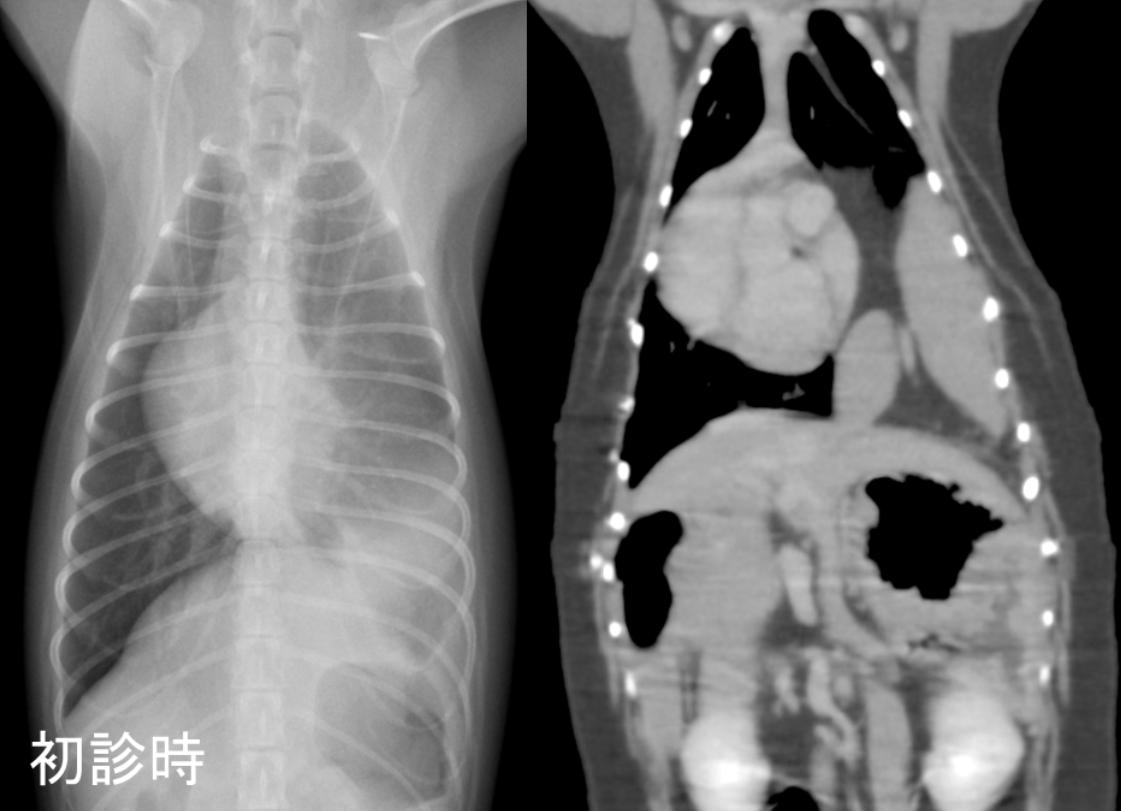

本人の状態や院内での身体検査、呼吸状態に異常は認められませんでしたが、麻酔前検査における胸部X線検査にて、左の肺に異常な白い領域が認められたため、後日CT検査を行いました。

CT検査においては、正常では横隔膜によって隔たれているはずの胸腔と腹腔のが連続しており、横隔膜左背側の孔からは左胸腔内へ脾臓が脱出していました。

そこで先天性胸膜腹膜ヘルニアを疑い、数日後に手術を予定していました。

初診時のレントゲン画像(左)、CT画像(右)